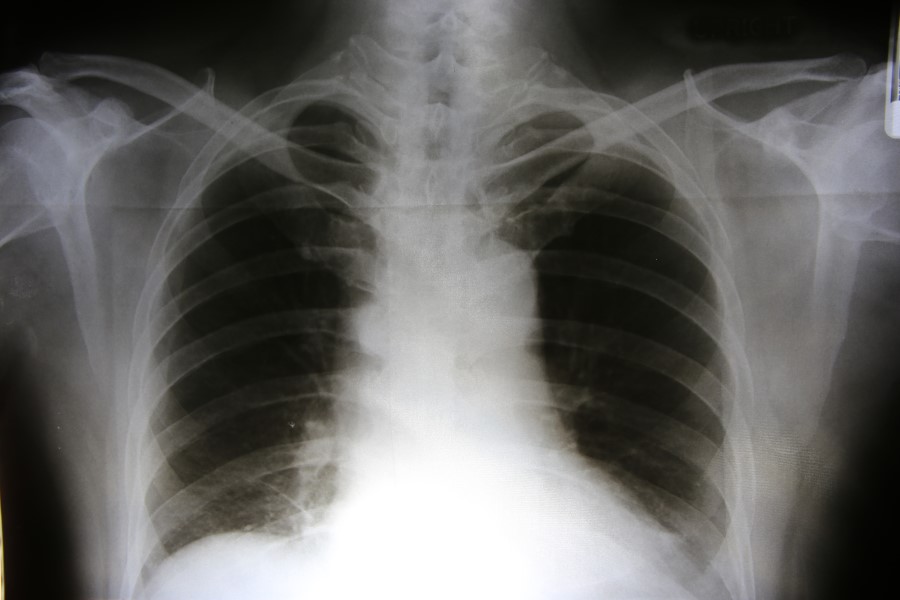

Następstwem zatorowości płucnej mogą być również zaburzenia rytmu serca, dlatego warto wykonać EKG. Chorzy z podejrzeniem zatorowości płucnej powinni także mieć zrobione zdjęcie RTG klatki piersiowej i USG żył głębokich kończyn dolnych, w niektórych przypadkach wykonuje się również angio-TK umożliwiające ocenę tętnic płucnych.